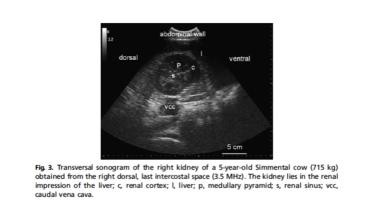

УЗИ моче-половой системы коров

Некоторое время назад разбиралась с УЗИ моче-половой системы коров (не совсем моя специализация). Надо признаться, это не рутинное исследование на фермах, потому даже в профилактических протоколах его нет. Более того, ...